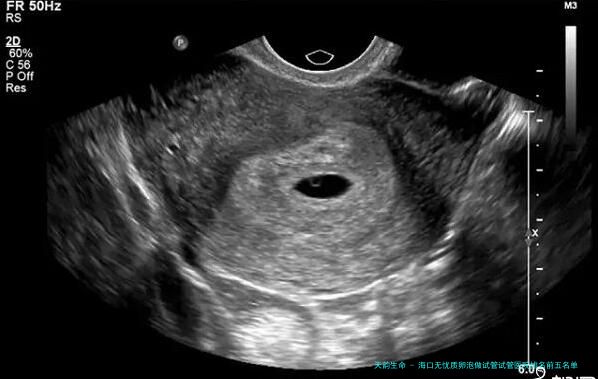

面对试管婴儿治疗,很多海口家庭焦急的不是“做不做”,而是“卵泡质量是不是达标?哪家医院技术更靠谱?”💡 毕竟,精良卵泡是成功的基础!今日就用新数据和实战经验,帮助你扫清迷雾!

根据卫健委资质、临床及患者反馈,海口可展开试管婴儿技术的医院内,下列十家在卵泡监测与个性化方案上症状凸起(数据综合2024-2025年统计):